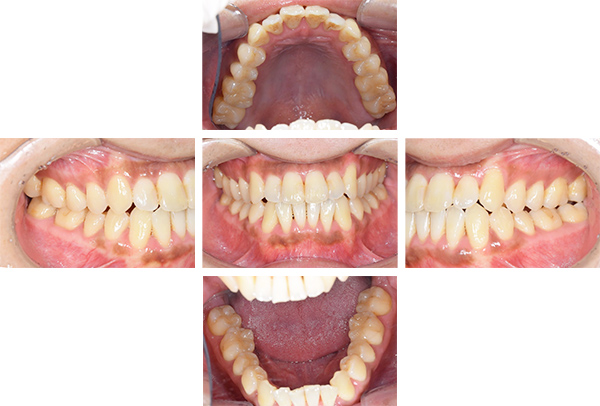

歯列矯正・インレー・クラウン症例

前歯が黒っぽいのが気になる、

悪いところは全部治したい

年齢 54代女性

主訴 歯をきれいにしたい

治療

期間

4年

費用 セラミックインレー 12本

660,000円

オールセラミックプレミアムクラウン 3本

495,000円

矯正 874,900円

計 2,029,900円(税込)

※全て税込となります。

症例写真(治療前)

担当医師所見

治療前:

八重歯が目立ちます。また銀歯もおおく、見た目が気になります。虫歯も散見できます。

レントゲン写真(治療前)

根の治療を3本すでに治療されています。1本根の奥の詰め物が疎になっていますので、根の部分の再治療も行う必要がありそうです。銀歯の中で虫歯になっているものもあります。

治療中

矯正装置をつけています。だんだん八重歯が動いてきているのがわかります。今回のケースでは、抜歯を行わずに矯正ができました。